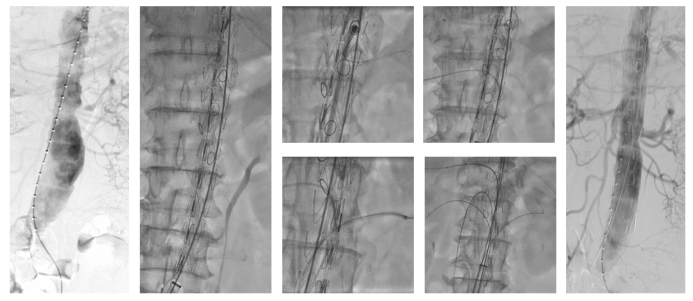

★ 支架改装策略

分支类型:根据患者内脏动脉开口的方向和病变性质(动脉瘤or夹层),可采用四种分支类型:

短内分支;短外分支;朝下分支;也可以选择人工血管加强环: 在分支开口处缝合一段人工血管,形成“烟囱”或“裙边”,能有效预防I型内漏,尤其适用于夹层或贴壁不良的情况。

束径:全程束径:根据患者解剖学特征,进行束径大小的调整;支架可前后、左右调整,保证超选成功率。